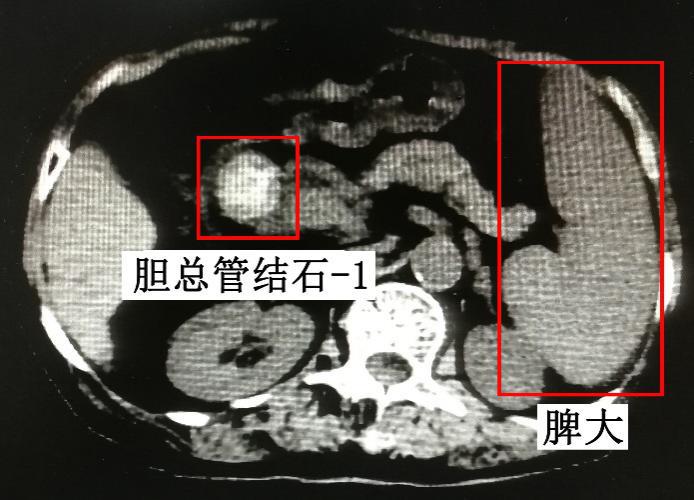

其家属急忙联系急救车送入我院急诊,急诊给予抗感染、护胃、护肝等治疗后,体温降至正常,但是仍有右上腹及剑突下疼痛,通过查上腹部CT结果提示:

1、胆总管结石(2枚),大小分别约12mm、26mm,肝内外胆管扩张,局部腹膜炎;

2、肝硬化,门脉高压,脾静脉、食管下段-胃底静脉曲张,脾大,少量腹水;

3、胆囊未见明确显示。